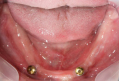

マグネット義歯

安定性

<マグネット>

<治療例>